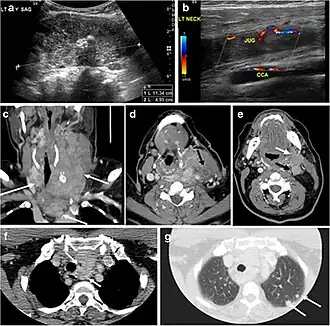

Fig. 13. A 27-year-old female patient known to have goiter. a, b Axial and sagittal enhanced CT scan images of the neck demonstrate a heterogeneously enhancing, enlarged thyroid gland with scattered calcifications (white arrow), cystic changes, and substantial retro-sternal extension (black asterisks). No lymphadenopathy or substantial airway narrowing.[1] -

Fig. 14. A 19-year-old male patient known to have multi-nodular goiter and FNA, showing underlying Hashimoto's thyroiditis. a, b Sagittal and transverse greyscale and colour Doppler ultrasound of the neck demonstrate a hypoechoic enlarged right thyroid lobe with small hyperechoic regenerative nodules and marked hypervascularity (white arrows). c, d Enhanced axial CT scan images of the neck demonstrate a heterogeneously enhancing and enlarged thyroid gland, left more than right lobe, and the trachea is markedly narrowed.[1] -

Fig. 15. A 33-year-old female patient who presented with neck swelling and pain and was later diagnosed with Hashimoto's thyroiditis. an Axial enhanced CT scan of the neck demonstrates minimal diffuse enlargement of the thyroid gland, especially the isthmus (white arrow). b Transverse greyscale ultrasound of the neck demonstrates heterogeneously enlarged thyroid and thickened isthmus, measuring 8.6 mm.[1]

Malignancy can coexist within the goiter and a CT scan may give a clue if there are abnormal cervical lymph nodes and/or signs of invasion. Retrosternal extension (Fig. 15) could affect the surgical approach, as a lower extent may require a partial or total sternotomy to facilitate complete resection. Therefore, the distance of the retrosternal extent from the sternal notch should be measured on a sagittal image.[1]